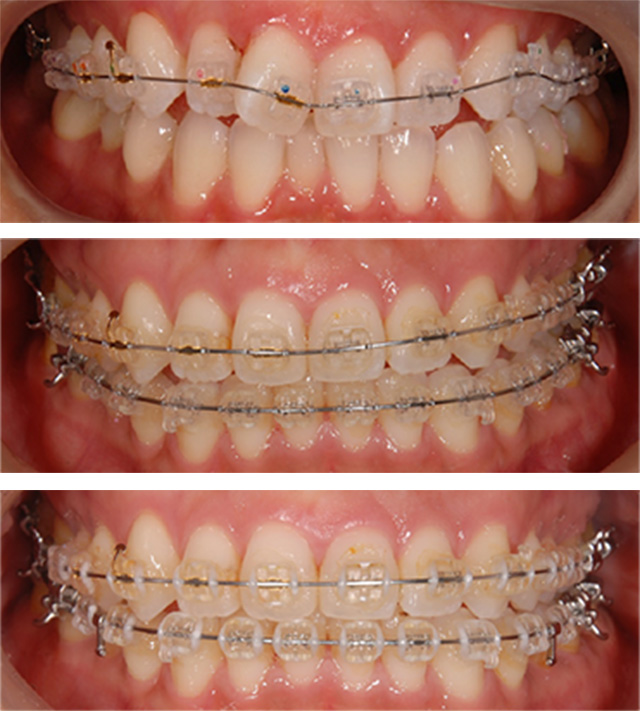

| 治療回数 | 36回 |

|---|---|

| 年齢・性別 | 30代 女性 |

| 治療期間 | 1年10ヶ月 |

| 治療費用 | 990,000円(税込) |

| 調整費 | 6,600円×来院毎(税込) ※2年目から |